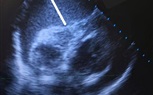

ومع المتابعة الدقيقة والمرور الطبي المنتظم، لاحظ الأطباء ارتفاعًا حادًا في معدل نبضات القلب، ما استدعى تحركًا فوريًا وإجراء رسم قلب كهربائي (ECG) وفحص الموجات الصوتية على القلب (Echocardiography)، لتكشف الفحوصات عن ارتشاح بالغشاء التاموري مصحوب بتأثير ضاغط على عضلة القلب، وهي حالة حرجة تتطلب تدخلًا عاجلًا دون أي تأخير.

وأسفر التدخل الدقيق والسريع عن سحب ما يقرب من 700 مل من السوائل من الغشاء التاموري، وهو ما انعكس مباشرة على الحالة العامة للمريض، حيث ارتفعت نسبة تشبع الأكسجين واستقرت العلامات الحيوية بصورة ملحوظة، في مشهد جسّد بوضوح قيمة القرار الطبي السريع المبني على خبرة علمية وتكامل مهني.